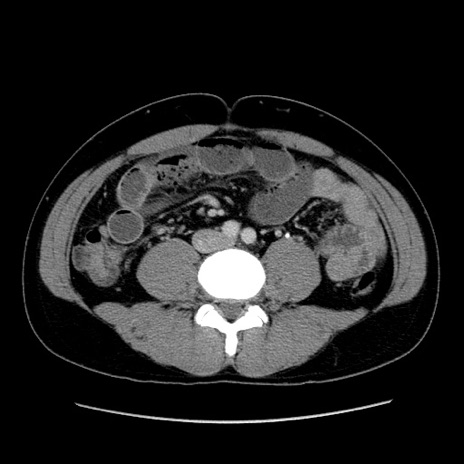

症例4(横断像)

【症例】30歳代男性

【主訴】腹痛、嘔吐

【現病歴】昨晩から突然の腹痛あり、その後嘔吐、軟便も出現。腹痛が改善しないため救急搬送となる。2日前にしめ鯖の食事歴あり。

【身体所見】意識清明、苦悶様、BP 135/90mmHg、BT 35.7℃、腹部:平坦、やや硬、心窩部〜臍部に自発痛、圧痛あり、筋性防御+、反跳痛-

【データ】WBC 8100、CRP 0.57